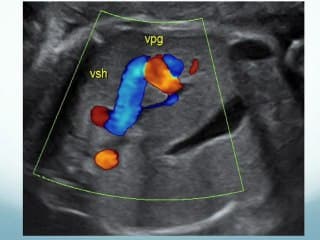

Très belles images didactiques d'un diagnostic rare, celui des fistules Porto-sus hépatiques. L'auteur à partir d'une série de 12 cas fait le point sur le diagnostic et la conduite à tenir à partir des complications observées.